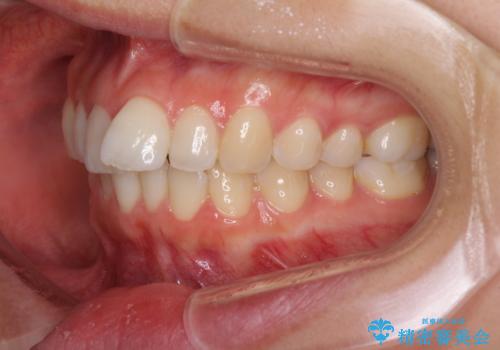

結婚式までに前歯を整えたいとのことでしたが、インビザラインでは先に奥歯を移動させてから前歯を動かすため、間に合わない可能性がありました。しかし、結婚式までに期間があったことと、マウスピースをしっかりと装着してくださったことで、十分な歯列に整えることができました。

楽しく通院していただき、辛いと思っていた治療もあっという間であったそうで、患者様には大変満足していただきました。